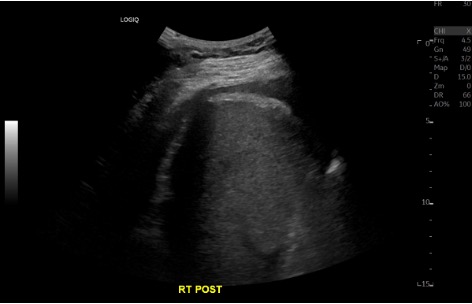

US survey — effusion + pre/post

Pre-procedure ultrasound showing right pleural effusion Pre-procedure CXR showing large left pleural effusion